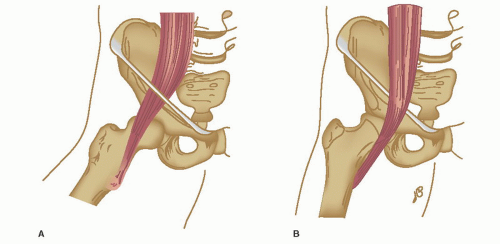

Patients with internal coxa saltans typically describe a painful clicking/popping sensation emanating from the deep, anterior groin. It is now well accepted that the source of pain and audible snapping is produced by subluxation of the iliopsoas tendon during hip range of motion.